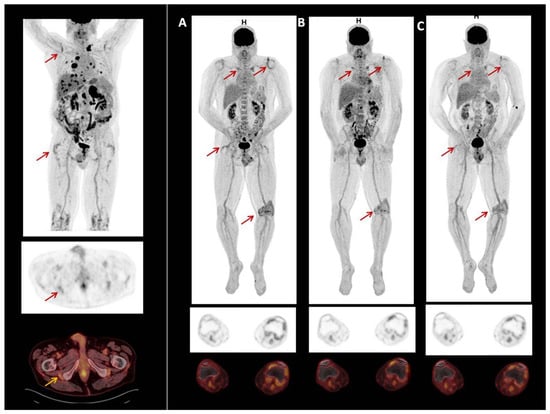

3.3. Patients with PET/CT Scan Assessment

Two male patients had PET/CT scans to study rheumatic irAE secondary to the use of ICI. Patient 1 had melanoma and was treated with Pembrolizumab. Patient 2 had prostate carcinoma and was treated with Atezolizumab and Cabozantinib. Neither had previous rheumatic disease. Both patients presented clinical PMR. PET-CT scans showed symmetric FDG uptake in the shoulder, hip joints, and greater trochanter and ischial tuberosities. One also showed FDG uptake in the left knee (Figure 6). The previous and our reports of PET/CT scan findings in rheumatic irAEs are shown in Supplementary Table S2.

Interestingly, some patients who underwent 18F-FDG PET before ICI therapy had some articular irAE-specific changes, which were exacerbated after immunotherapy [25,26,27,40]. As suggested by van der Geest et al., we agree that although this mild metabolic activity may also be seen in non-inflammatory conditions, it could suggest that low-grade, subclinical inflammation may already have been present at these sites before ICI therapy and was potentiated after treatment [26]. Inflammatory changes in multiple joints found by PET/CT in patients in this study probably reflected an autoimmune cellular attack on the synovia [28]. Here we report two consecutive patients with ICI-induced arthritis who presented PMR-like disease with 18F-FDG PET/CT showing symmetric FDG uptake in the shoulder, hip joints, greater trochanter, and ischial tuberosities, in accordance with the clinical signs.

Figure 6. 18F-FDG PET/CT image of patient with prostate carcinoma treated with Atezolizumab and Cabozatinib. Symmetric FDG uptake shoulder, hip joints, greater trochanter and ischial tuberosities. Also show, FDG uptake in left knee (A). In 2020, due to irAEs ICI were discontinued. After discontinuation of treatment, uptake decreased (B,C).